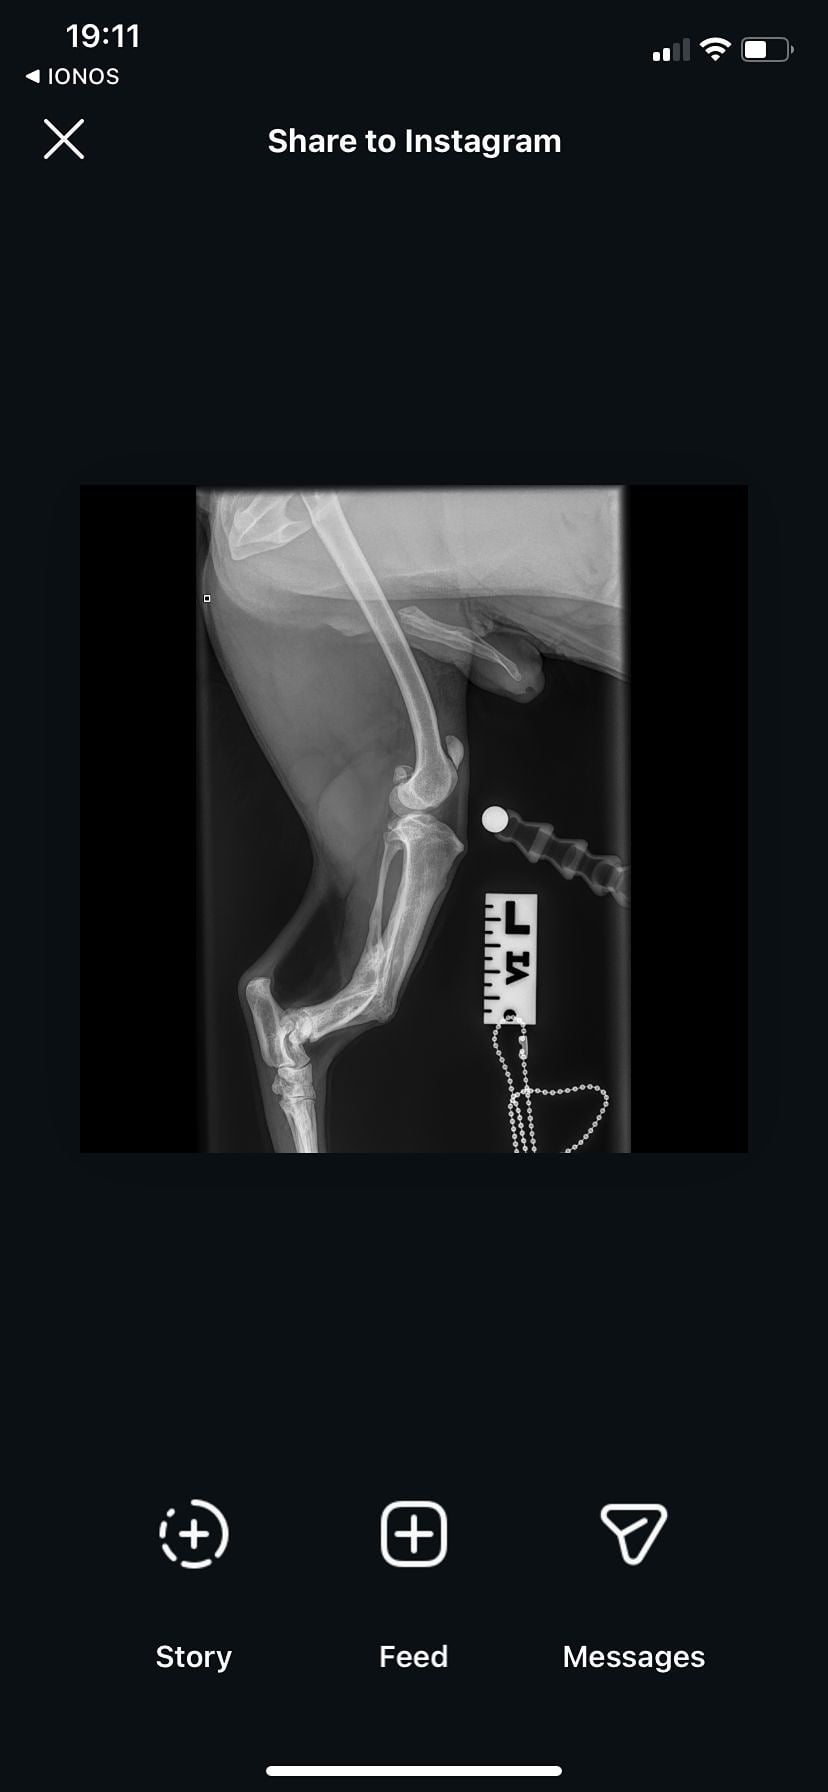

Upon arriving at Oakwood, we noticed Billi was not fully weight bearing on his BL leg. We put him on pain meds and kennels rest but when this wasn't working, we sent him straight from X-rays.

Unfortunately, Billi has several problems with his legs that are going to require surgical intervention.

His back right leg: He has luxating patella grade 2

His left leg: He has luxating patella grade 3/4. He also has an old break that has healed completely abnormally in this leg, you can feel the bone almost protruding through his skin, even with the gentlest touch.

To make the surgery even more difficult, the break has healed so abnormally that it has left Billi with a leg 2 inches shorter than his other. His hips are also at a 20% rotational angle which doesn't effect Billie is every day life, but will effect the difficulty of the surgery and so we are currently in discussions with specialists as to what the best plan of action is going to be.